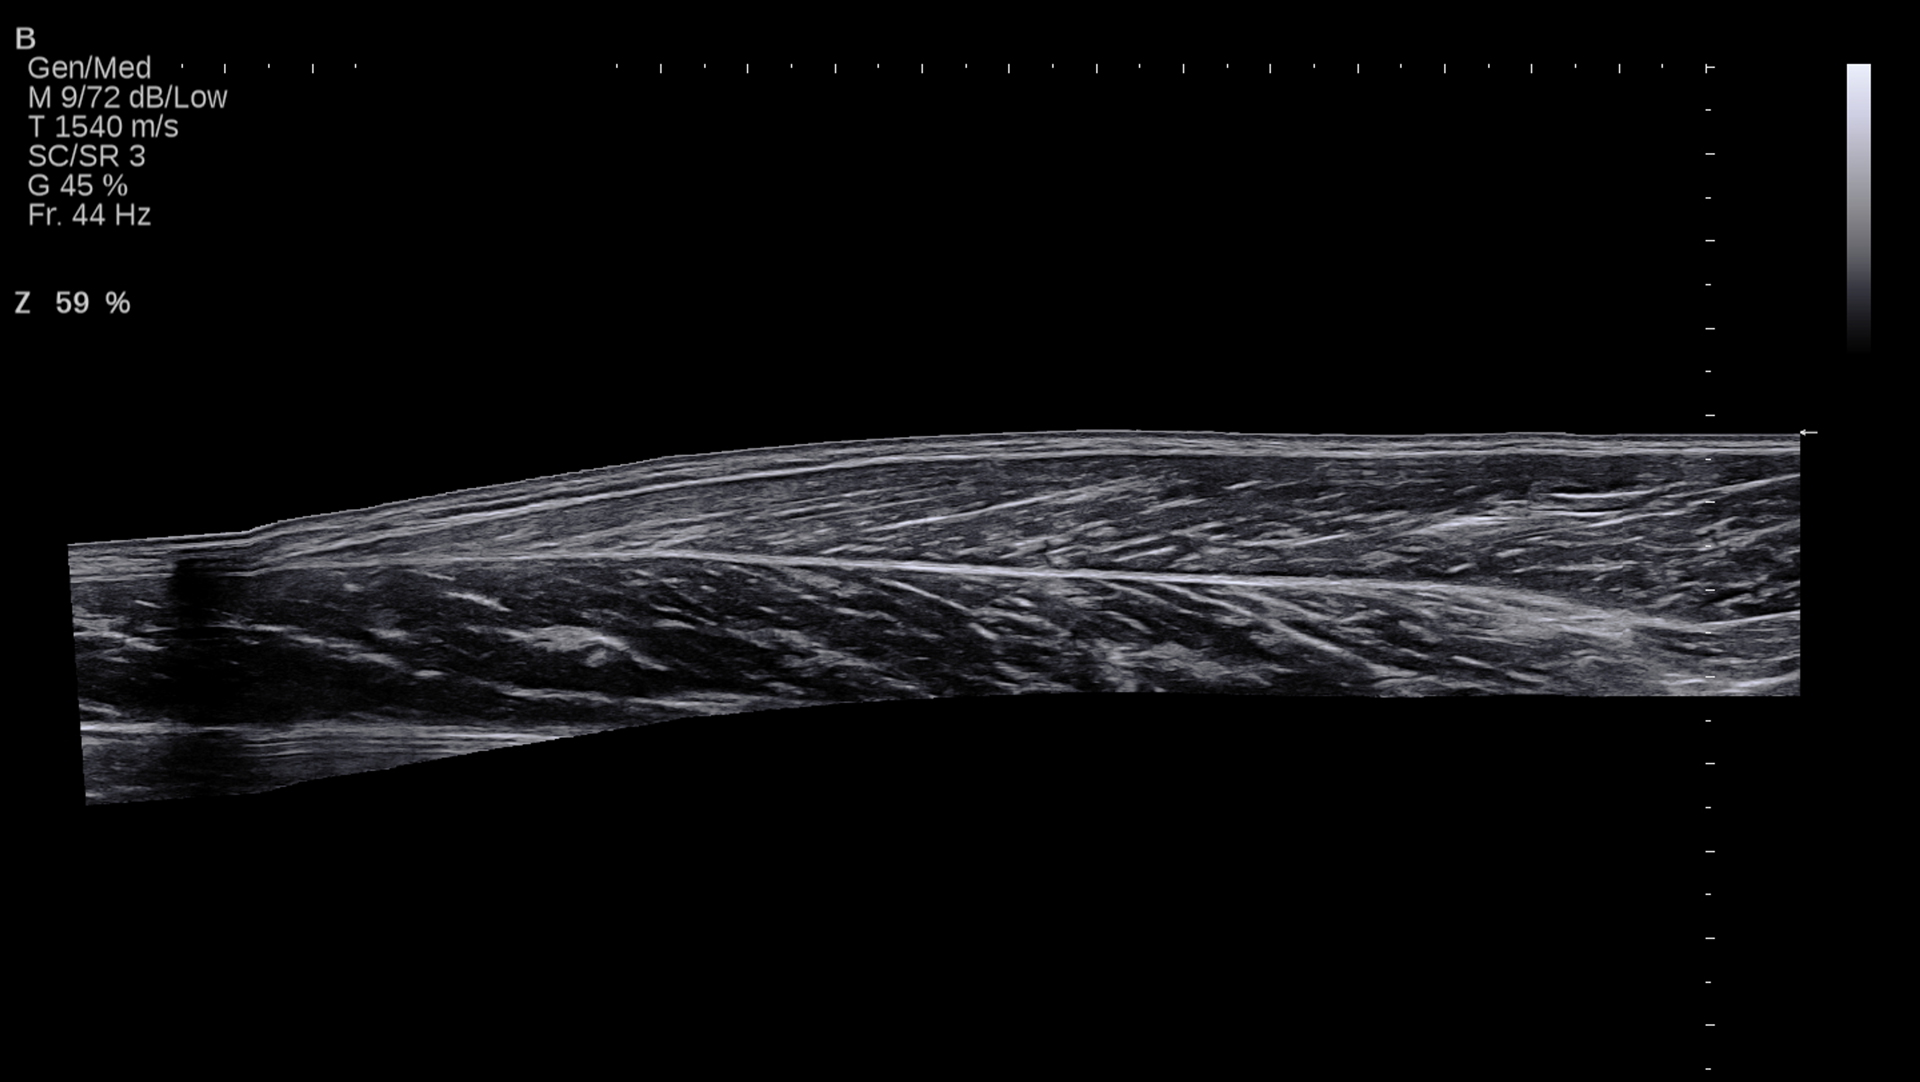

- 医用画像(超音波・MRI)解析による筋腱複合体の形態学的研究